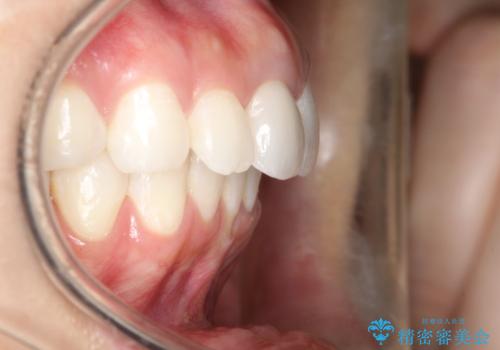

- ワイヤーで矯正した後戻りをマウスピースで治そうとしたが、使えなかったため再度ワイヤー矯正希望で来院されました。

装置はハーフリンガルを選択しています。

矯正としてはマウスピースでできましたが、患者さんの希望でワイヤー(ハーフリンガル)で矯正を行いました。